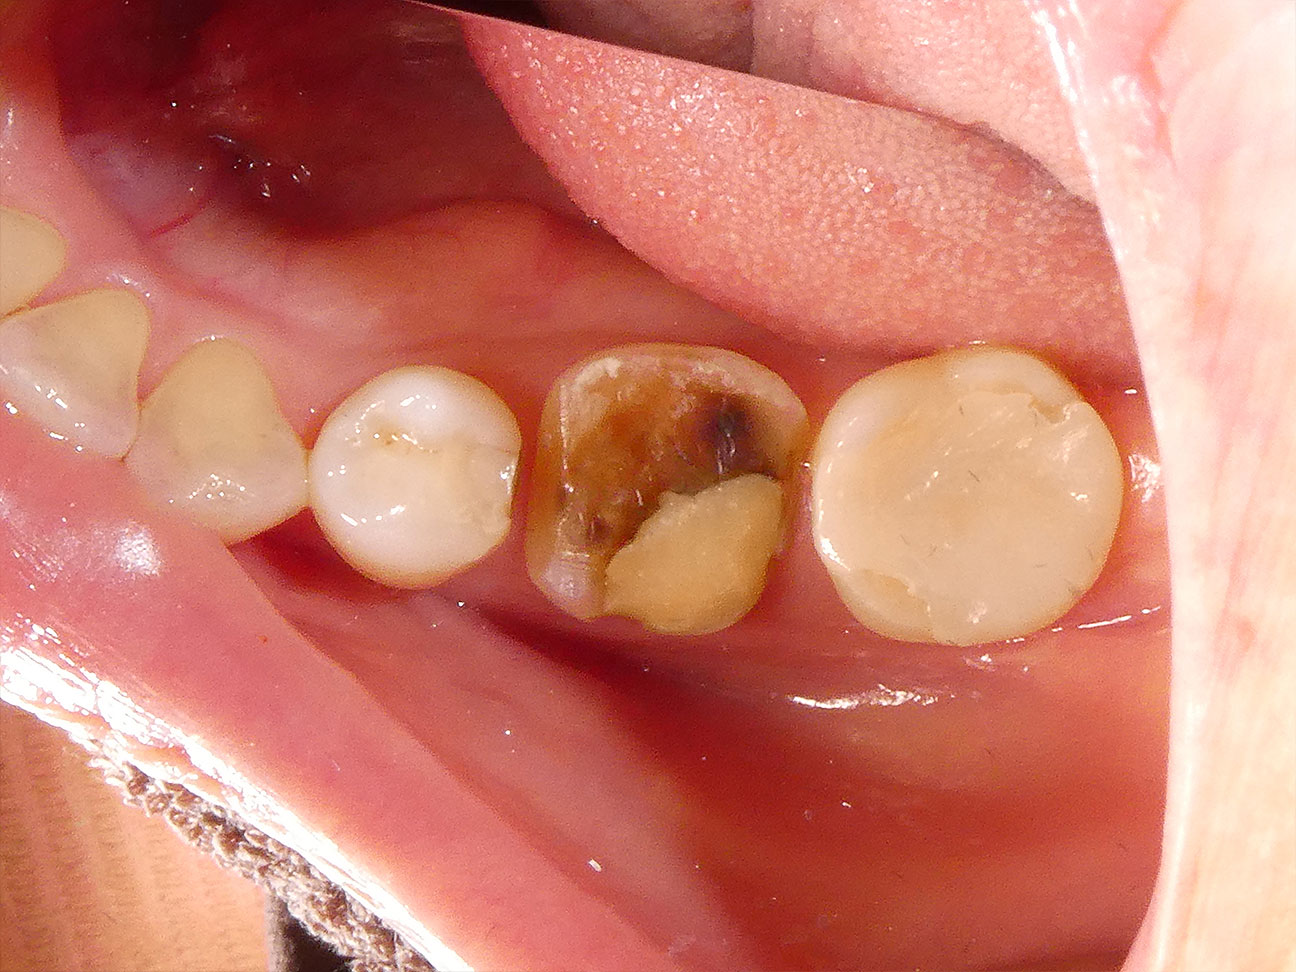

STEP5 保険の銀歯の脱離

奥歯の治療から約3ヶ月後に、保険で治療した金属の被せ物が取れてしまったということでご来院になりました。ご覧のとおり以前あった保険の銀歯がなくなっています。最初のプラスチックの詰めものをジルコニアインレーで修復する際にもお伝えしましたが、噛みしめ・食いしばり傾向の強い患者さんのため、特に力の大きく加わる奥歯はの治療はどうしても保険治療の範囲では限界があります。